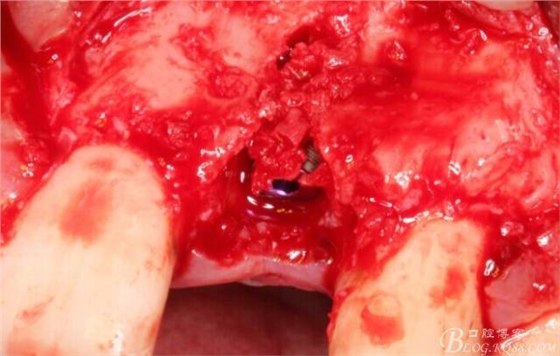

植入植體。